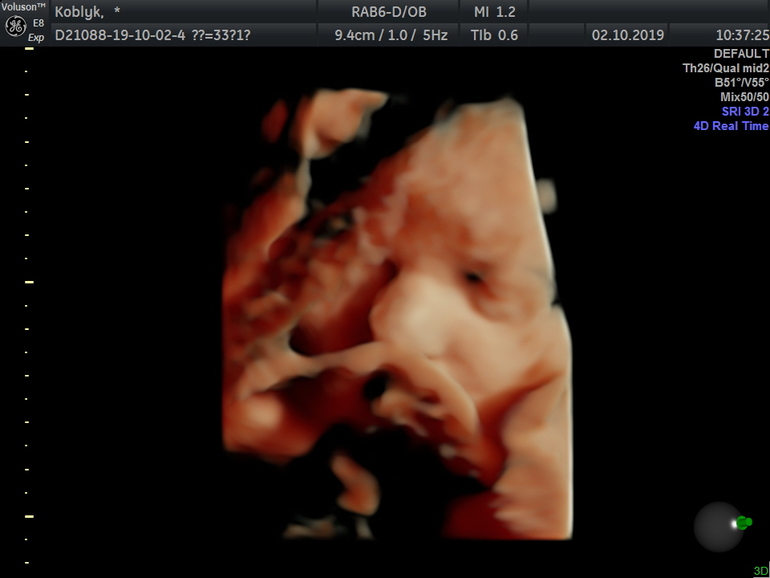

Предлежание головное, вторая позиция, передний вид. Дочка скрутилась клубочком, и ручки, и ножки возле головы слева внизу, во время УЗИ чмякала ротиком, посасывала пальчик на ручке, а потом и на ножке)) В связи с этим не получилось сделать хорошего фото ее мордашки, зафоткали только кусочек.😔 Хотя по-моему все дети на этом 3д выглядят одинаково😁